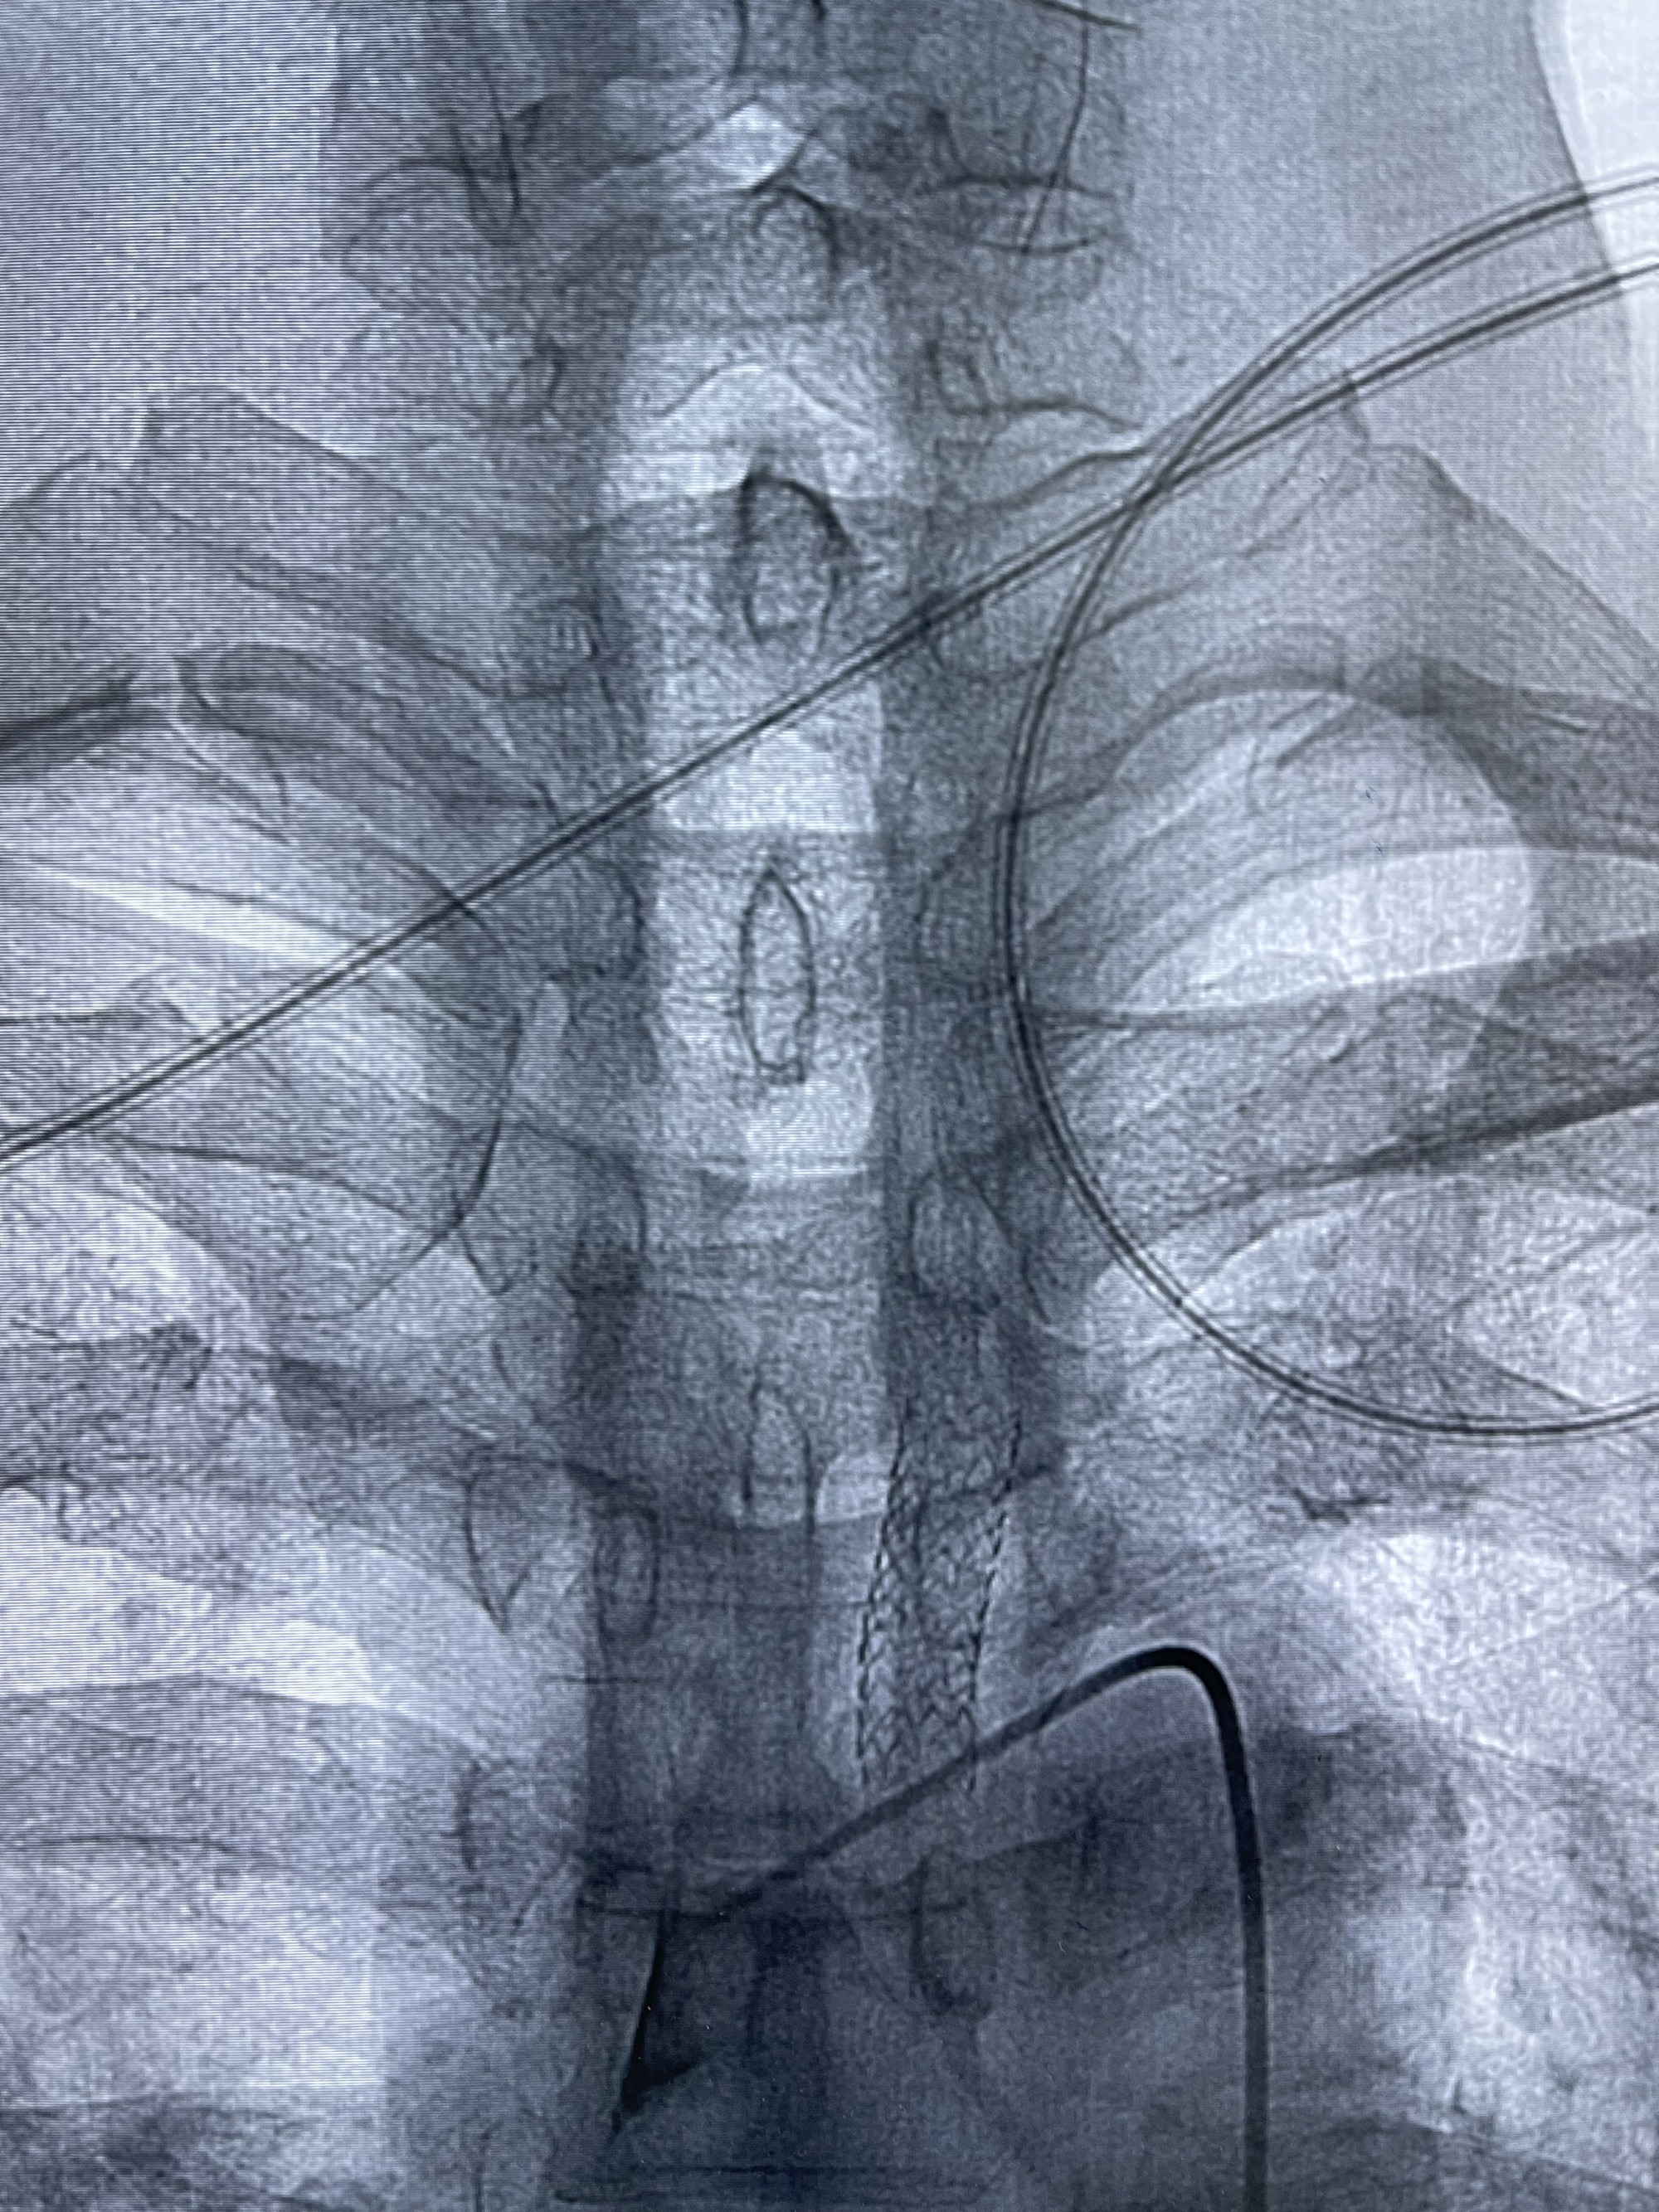

脑血管造影2023.03.06:右侧颈内动脉颈段至岩骨段闭塞,可见后后循环通过原始三叉动脉吻合代偿至海绵窦段,后交通区可见囊状造影剂填充影,左侧锁骨下动脉呈“残端”改变,呈“右侧颈总动脉支架成形术后改变”,支架内血流通畅,可见后交通吻合显影至左侧大脑后动脉,并可见左枕动脉吻合椎动脉至锁骨下动脉

2023-03-06DSA:

1.右侧颈内动脉及左侧锁骨下动脉闭塞

2.右侧颈内动脉由后循环经右侧后交通动脉前向代偿显示

3.右侧颈内动脉眼动脉段近后交通动脉处重度狭窄伴前壁不规则动脉瘤

4.右侧颈外动脉可见经由右侧脑膜中动脉吻合显影右侧眼动脉及颈内动脉

5.左侧颈总动脉起始部支架术后

6.左侧颈外动脉可见吻合显影至左侧椎动脉并逆行供血至左侧腋动脉

7.左侧锁骨下动脉闭塞

1.箭头处为右侧颈内动脉后交通动脉处重度狭窄,狭窄前壁为不规则动脉瘤;

2.狭窄远端颈内动脉由左侧颈内动脉经左侧后交通动脉—基底动脉顶—右侧后交通—右侧颈内动脉—右侧大脑中动脉途径代偿

左侧颈内动脉经左侧后交通动脉—基底动脉顶—右侧后交通—右侧颈内动脉—右侧大脑中动脉途径代偿

左侧颈外动脉经脑膜支吻合至左侧椎动脉—左侧锁骨下动脉—左侧上肢